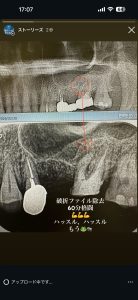

破折ファイル除去

60分かかりやっと除去、30分以内にやらないとね💦

反省点かな、スピード大切